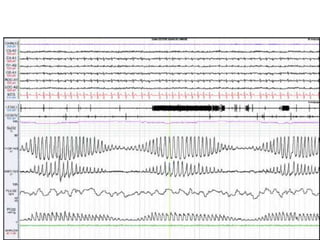

VPC, tachycardia in OSA pt

After CPAP